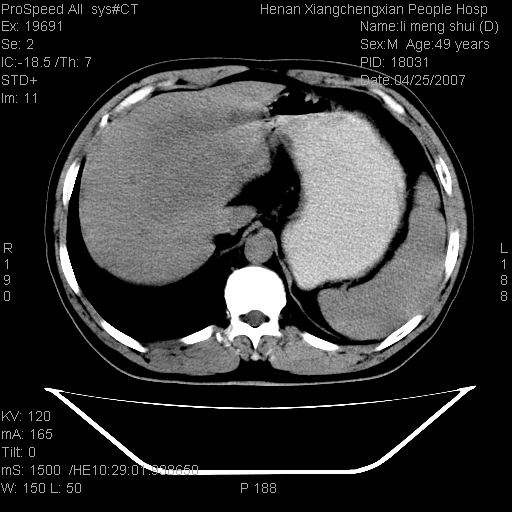

| 患者,男,49岁, 腹疼伴恶心\\呕吐20天,20天前无明显诱因出现右上腹部疼痛,钝疼,无放射,伴恶心\\呕吐,不伴发热.患者不愿增强. b超:肝脏右叶实性占位. ct:肝脏右叶可见一巨块状圆形低密度影,大小约93mm*84mm,其内可见点状高密度影,胆囊、胰腺、脾脏大小、形态及密度未见异常,腹膜后间隙未见肿大淋巴结影。 印象:肝脏右叶巨大肿块,性质待定,建议增强并穿刺活检进一步确诊。 ct平扫: ![]() ![]() ![]() ![]() ![]() ![]() ![]() ![]() ![]() ![]() ![]() ![]() ![]() ![]() ![]() ![]() ![]() 肝脏右叶肿块ct引导下穿刺活检术 患者于16时05分仰卧于ct检查台上,首先行肝脏ct扫描确定进针位置、深度、角度。在局麻下行ct引导下肝脏右叶肿块穿刺活检术。常规消毒、铺巾、局麻。在ct引导下使活检针经右侧腋中线、第9肋间隙垂直胸壁进针90mm,针头进入病变预定位置。在病变预定位置多点、多方向抽取小米样病变组织多块,涂片五张送病理检查。术后穿刺点局部无出血,未出现腹腔积液等并发症。术中及术后患者生命体征稳定,手术于17时10分成功完成。患者安返病房。 穿刺片 ![]() ![]() ![]() ![]() ![]() ![]() ![]() ![]() ![]() ![]() ![]() ![]() ![]() ![]() ![]() ![]() 病理结果肝细胞癌 ![]() 原贴地址:http://www.radinet.com.cn/forum_view.asp?forum_id=4&view_id=24130 ok |